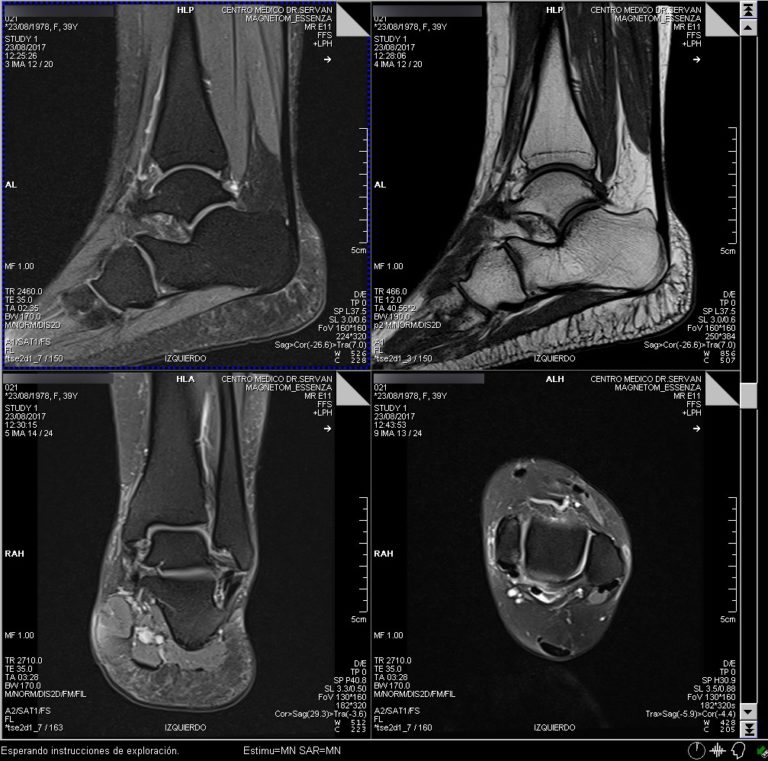

Web la resonancia magnética es el método de imagen idóneo para el análisis de las lesiones en los tejidos blandos. Web la rm del tobillo está indicada en pacientes con lesiones traumáticos, dolores inespecíficos, distensiones, tumefacción, hematomas e infecciones. Manual de supervivencia para el radiólogo que empieza.

Web la resonancia magnética (irm) utiliza un campo magnético, ondas de radio y una computadora para crear cortes de imágenes detalladas (secciones transversales) de las. Web la rm de tobillo puede dar imágenes de desgarros muy pequeños, lesiones tendinosas, ligamentos y músculos, y hasta algunas fracturas que no se pueden ver en la radiografía. Web la resonancia magnética utiliza ondas de radio y un fuerte campo magnético para crear imágenes muy detalladas de los ligamentos que ayudan a.